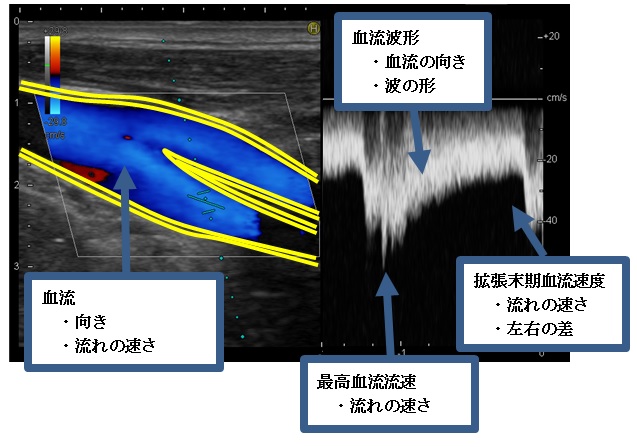

次の画像は血管超音波検査の一つである頸動脈の画像で、模式図・超音波画像断層図及び血流波形です。

この画像はもっとも病変が生じやすいといわれる「分岐部」で、血管が枝分かれしている部分です。

この画像で検査している項目の一例です。

※比べやすいように黄線を入れています。

実際は白黒の画像です。